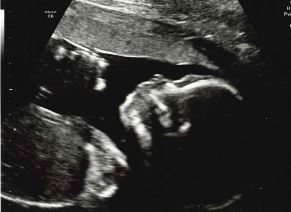

I am so in love with my baby already and can't wait to meet him, just needed to share that.